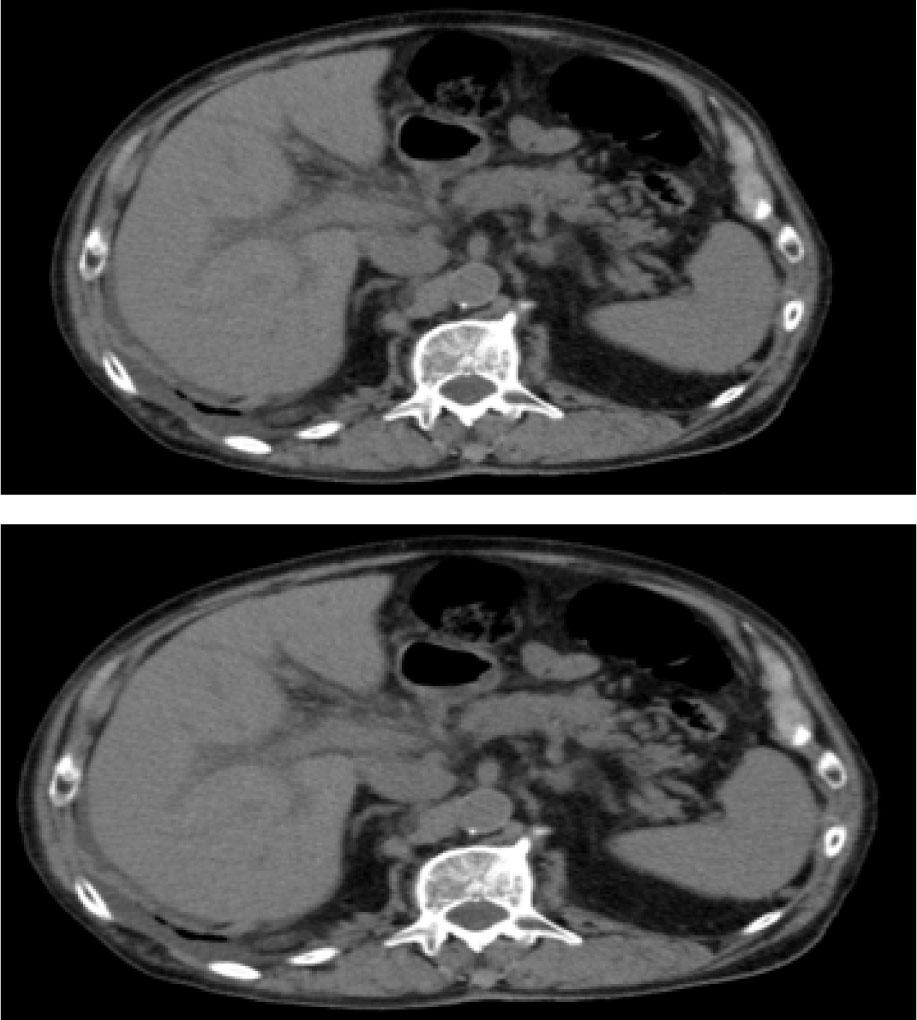

During the patient's hospitalisation in our department, an abdominal CT was performed, and it was negative for liver metastases or any other hepatic parenchyma lesions (Fig. 1). A pelvis CT revealed stable disease regarding pelvic lymph node metastases. Blood tests of viral hepatitis were negative. The patient denied alcohol consumption.

Figure 1

Abdominal CT performed during hospitalization.